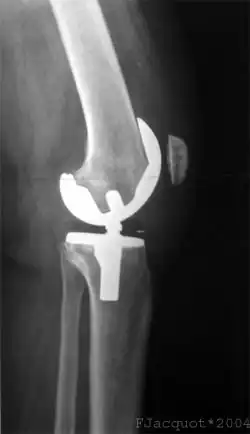

Gonartrosis

La gonartrosis es la artrosis de rodilla. Puede afectar a la articulación femorotibial y a la femororrotuliana. Es más frecuente en mujeres que en varones y suele aparecer a partir de los 50 años. Produce dolor que aumenta al caminar, incapacidad funcional y deformidad en genu varo o genu valgo que se agrava progresivamente con el paso de los años.

Para el diagnóstico es muy útil la radiología, en la que aparecen signos característicos, como estrechamiento del espacio articular, esclerosis subcondral y presencia de osteofitos.

Los factores principales que influyen en la aparición de artrosis de rodilla son la edad, la predisposición genética, la obesidad, la existencia de traumatismos previos y la sobrecarga de la articulación. El tratamiento es conservador en las primeras etapas de la enfermedad y se basa en realizar ejercicios de rehabilitación y medicamentos antiinflamatorios en los periodos de dolor agudo. Cuando la artrosis está muy avanzada y produce graves repercusiones funcionales, existe indicación para la sustitución quirúrgica de la articulación de la rodilla por una prótesis.[34]